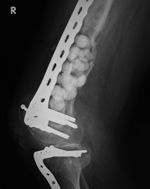

The antibiotic laden cement beads were placed in an area of infected bone after an open fracture. A periarticular locking plate is in the distal femur, and a buttress plate and interfragmentary screws are in the tibia.

Antibiotic beads